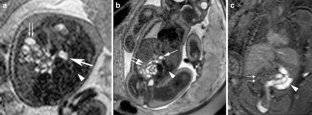

We report a case of intestinal malrotation without any associated GI tract complications diagnosed antenatally by fetal MRI. Antenatal US revealed a midline stomach. Subsequent fetal MRI confirmed the midline stomach and, in addition, revealed all loops of small bowel to the right of the midline and all large bowel to the left. All these features were consistent with intestinal malrotation. There was no abnormal bowel wall thickening, bowel dilatation, ascites or polyhydramnios. To our knowledge, this is a unique case of intestinal malrotation without associated GI tract complications diagnosed antenatally on fetal MRI.

Fig. 2